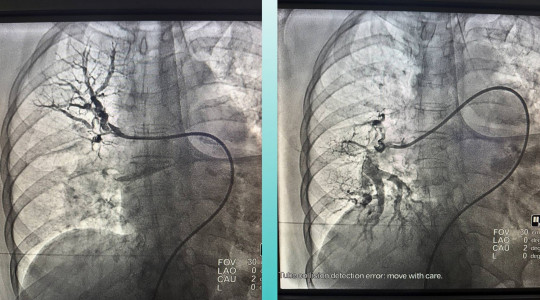

Окрім цього, лікарів насторожили скарги пацієнтки на утруднене дихання. Додаткове обстеження легенів підтвердило ще один небезпечний діагноз — тромбоемболію легеневої артерії.

З огляду на критичний стан жінки, мультидисциплінарна команда медиків ухвалила відповідальне рішення — провести одночасну тромбектомію з мозкової та легеневої артерій.

Оперативне втручання минуло успішно. Стан пацієнтки значно покращився: вона при свідомості, з’явилися активні рухи в кінцівках.